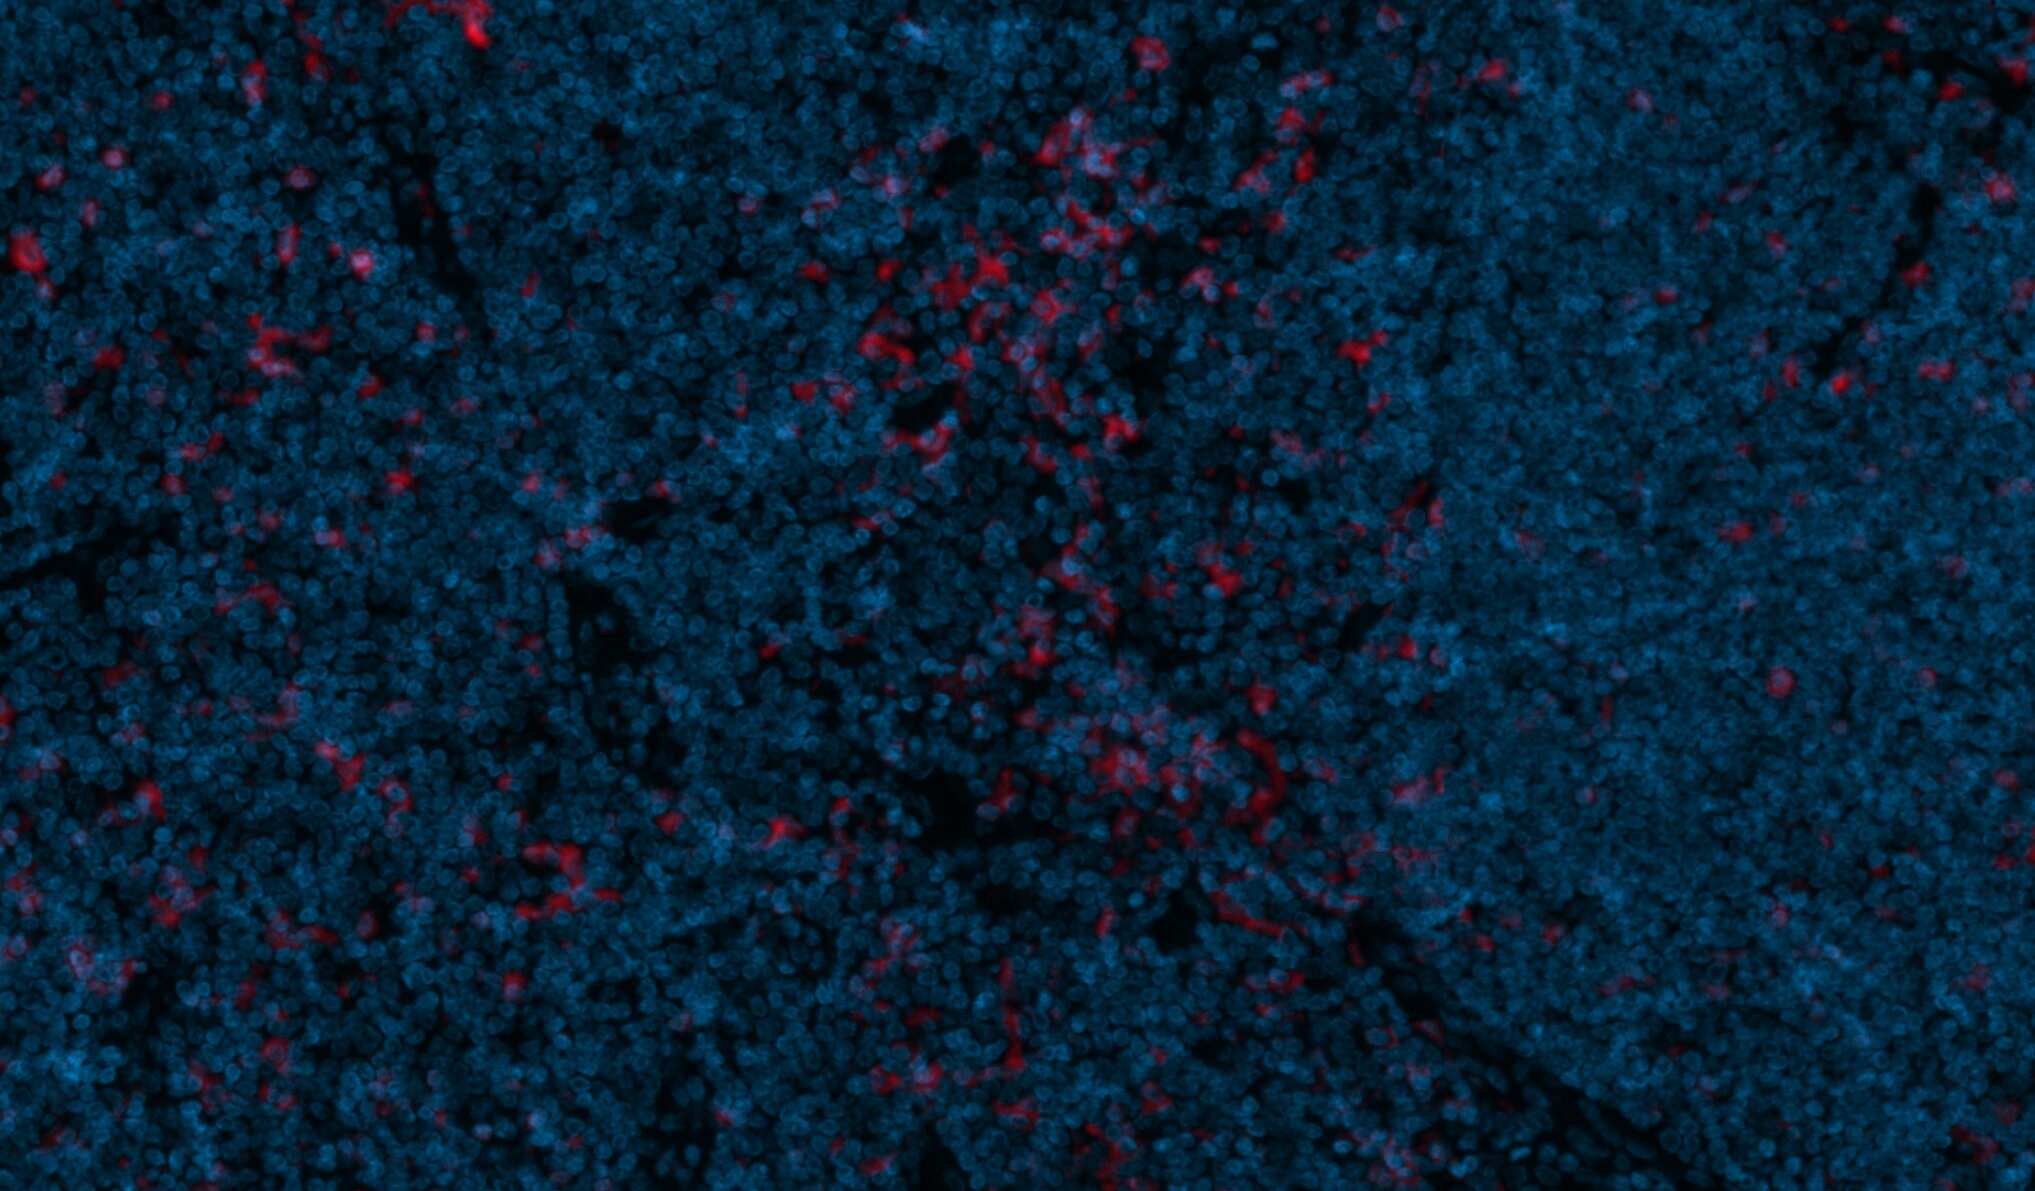

Immunohistochemistry-Paraffin: Mouse Monoclonal CD11c Antibody (ITGAX/1243) - Azide and BSA Free [NBP2-54432] -

Immunohistochemistry-Paraffin: Mouse Monoclonal CD11c Antibody (ITGAX/1243) - Azide and BSA Free [NBP2-54432] - CD11c was stained in human FFPE tonsil tissue. HIER antigen retrieval was performed at pH 9 for 20min. Concentration used: 1:50. AF750 conjugated version of the antibody was used (Catalog # NBP2-54432AF750). Image from a verified customer review.